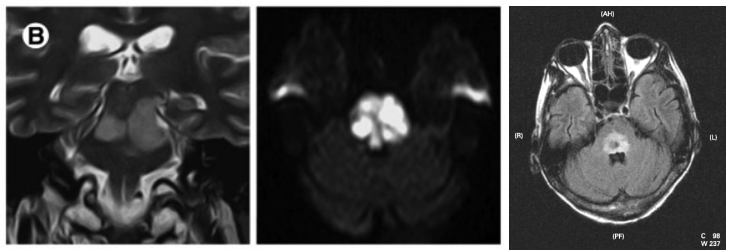

1、脑干毛细胞型星形细胞瘤:儿童患者较常见的神经胶质肿瘤,也是较常见累及小脑的肿瘤。值得一提的是该肿瘤有良性的生物行为,10年生存率达94%,大部分发生于20岁以前患者。小脑、视神经、视交叉及下丘脑是较常见的发病部位,但是该肿瘤也可发生于大脑半球、脑室及脑干。MRI通常表现为囊性肿块伴壁结节强化,有时候也表现为实性肿块无瘤周水肿,在脑干,其通常累及中脑及延髓,而浸润型胶质瘤通常累及脑桥。

(横断位T1WI示一低信号肿块累及脑桥延髓交界区,T2WI及FLAIR呈高信号;横断位、冠状位、矢状位T1WI C示片状、不规则形强化)

(矢状位及横断位T1WI示中脑及脑桥上部见一囊性肿块伴壁结节)

浸润性脑干星形细胞瘤:星形细胞瘤通常位于脑的某些区域,在成人,浸润型星形细胞瘤通常位于大脑半球(75%),在儿童,浸润型星形细胞瘤通常位于脑干,毛细胞型星形细胞瘤通常位于小脑。浸润性星形细胞瘤通常侵犯脑干,但导致其损害,它可以发生恶性转化。

横断位T2WI及FLAIR示脑桥高信号肿块,横断位及矢状位T1WI C示一膨胀性肿块累及脑桥并向中脑和延髓延伸,增强未见强化。